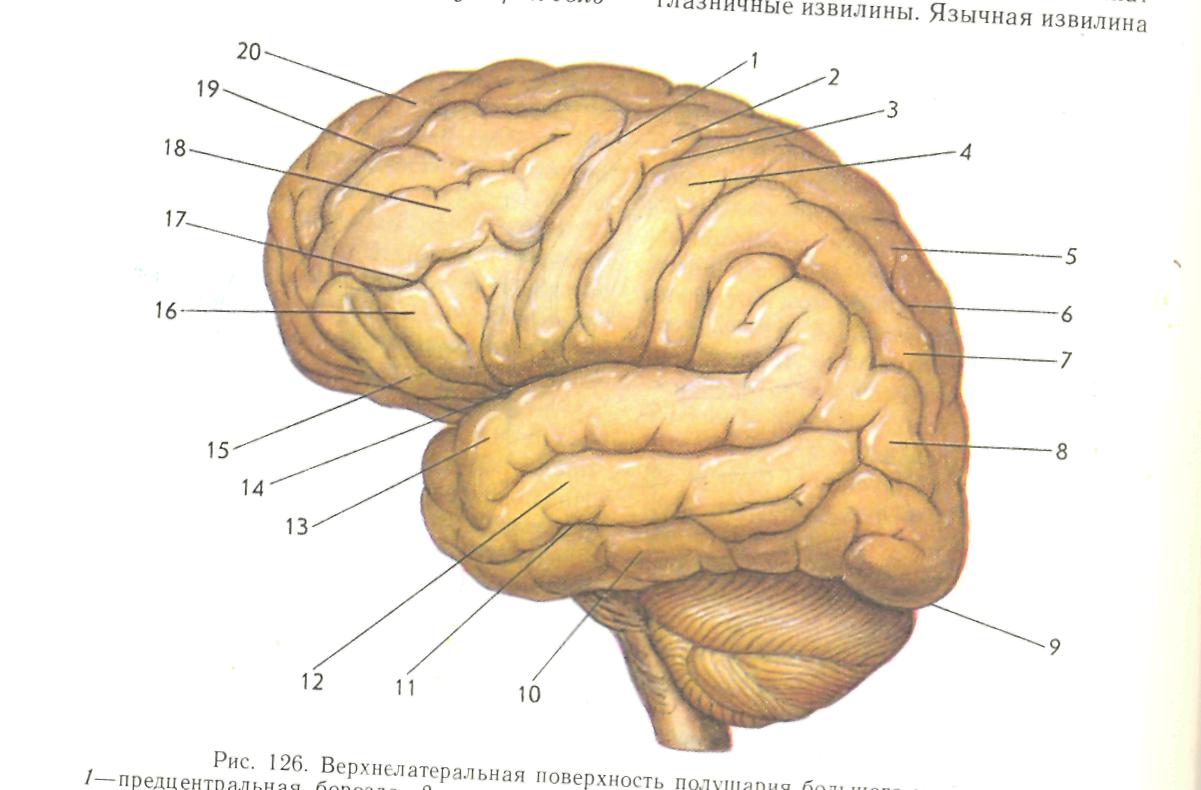

Анатомические снимки верхнелатеральной поверхности головного мозга